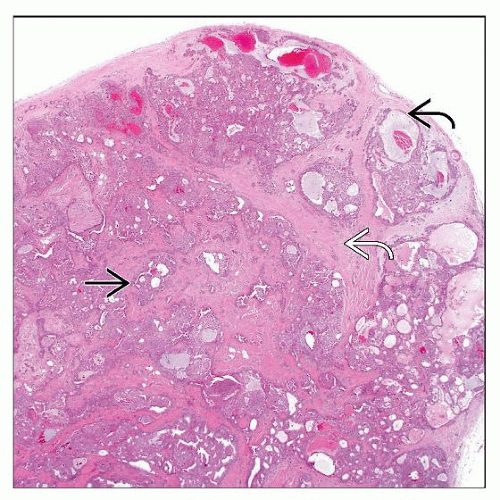

lipofibromatous tumors – Humpath.com – Human pathology

Spindle cell lipoma is composed of a proliferation of adipocytes and …

Pathology Outlines – Atypical lipomatous tumor / well differentiated …

Atypical Lipomatous Tumor/Well-Differentiated Liposarcoma …